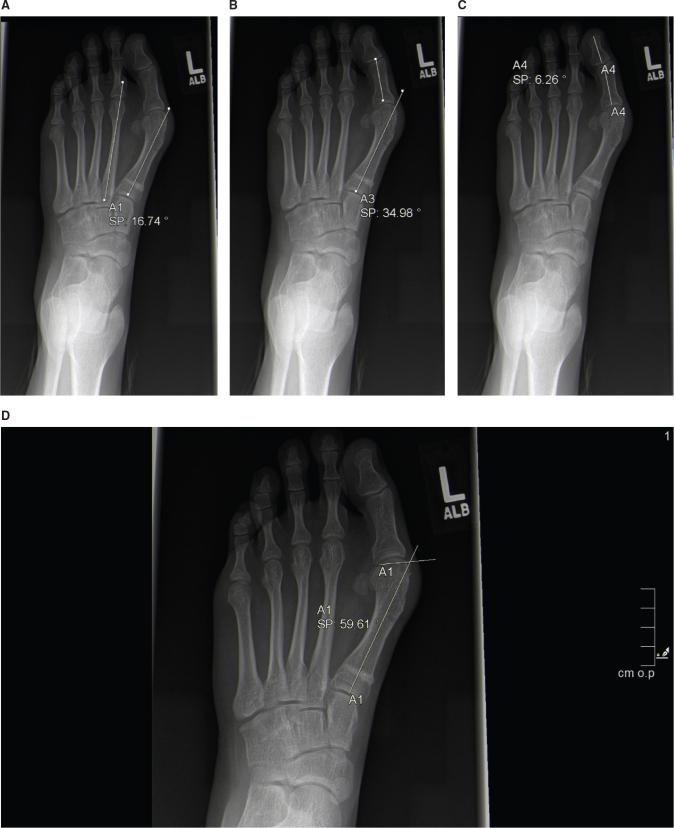

Surgical correction of adolescent hallux valgus (AHV) is accompanied by high rates of recurrence. Thus, surgery in the adolescent age group should only be undertaken in fully informed patients with pain refractory to nonoperative measures. A subset of patients with AHV may manifest hypermobility of the 1 tarsometatarsal joint (TMTJ), which may lead to recurrence. The Lapidus or modified Lapidus procedure involves TMTJ fusion and is a powerful and durable procedure for correcting metatarsus primus varus (MPV) and thus hallux valgus. Furthermore, it can reliably correct pronation of the 1 metatarsal, which may contribute to high recurrence rates. As many pediatric orthopaedists may be unfamiliar with this operation, we discuss patient evaluation and preferred technique for the performance of the Lapidus procedure. •Hypermobility of the 1 ray leads to metatarsus primus varus and hallux valgus and is likely a mechanism for recurrence after AHV surgery.•Standing radiographs disclose an increased 1/2 intermetatarsal angle (IMA) and excessive dorsiflexion of the 1 ray. Hypertrophy of the cortex of the 2 metatarsal is variable.•1 TMTJ fusion can result in lasting correction of MPV and AHV.•It is imperative that cartilage resection proceeds all the way plantar (3 cm) to allow for adequate plantarflexion of the 1 ray. Minimal resection prevents excessive shortening and internal fixation should be rigid.

•站立位X线片显示第一/二跖骨间角(IMA)增大以及第一跖骨过度背屈。第二跖骨皮质增厚情况不一。